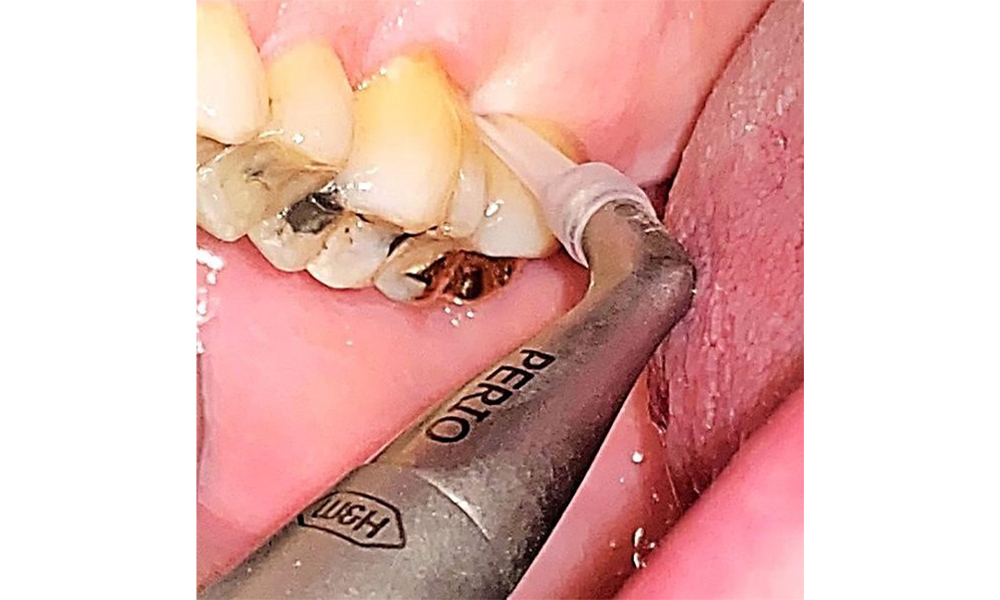

There are no limitations regarding the choice of instrumentation methods. Regular supragingival and subgingival instrumentation is essential to prevent disease progression due to the pre-existing periodontitis and high risk of recurrence. There are no limitations placed on the selection of instruments for mechanical biofilm removal from a general medical perspective, and removal should be performed as needed. Hard and mineralized plaque, such as calculus and concretions, should be removed using manual instruments or sonic/ultrasonic scalers (Fig. 9) (8, 9).

Use an ultrasonic tip to remove hard, mineralized plaque (Proxeo Ultra scaler with the Perio tip, W&H, shown here). © Dr R. Krapf

Fig. 9: Use an ultrasonic tip to remove hard, mineralized plaque (Proxeo Ultra scaler with the Perio tip, W&H, shown here). © Dr R. Krapf

Supragingival and subgingival biofilm removal is indispensable for maintaining the stability of the periodontal condition. Air polishing using low-abrasive powder is suitable for this purpose. Periodontal pockets and exposed root surfaces must be cleaned with low-abrasion powders. The use of a flexible parotip is recommended for patients with increased probing depths (deeper than 5 mm) (Fig. 10). (9)